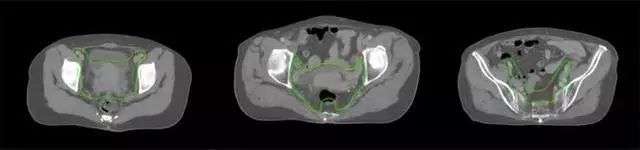

四、放射治療智能勾畫(huà)軟件

產(chǎn)品背景

放射治療,簡(jiǎn)稱(chēng)放療,是治療腫瘤主要手段之一,利用放射線(xiàn)破壞照射區(qū)(靶區(qū))的細(xì)胞,使腫瘤細(xì)胞停止分裂直至死亡,醫(yī)生通常把放射治療形象的比喻為“打靶”,放療前精準(zhǔn)勾畫(huà)腫瘤靶區(qū)范圍是腫瘤放射治療的關(guān)鍵步驟。傳統(tǒng)的靶區(qū)勾畫(huà)醫(yī)生會(huì)根據(jù)患者多張CT、MRI影像片憑借經(jīng)驗(yàn)進(jìn)行,比較耗時(shí),治療的病人數(shù)量也有限,且靶區(qū)勾畫(huà)缺少行業(yè)統(tǒng)一的規(guī)范和標(biāo)準(zhǔn),無(wú)法達(dá)到同質(zhì)化,勾畫(huà)精確度不理想。

技術(shù)原理

基于深度學(xué)習(xí)人工智能的放療靶區(qū)智能勾畫(huà)技術(shù)和自動(dòng)計(jì)劃技術(shù),基于全面的市場(chǎng)調(diào)研和臨床專(zhuān)業(yè)意見(jiàn),采用獨(dú)創(chuàng)的基于小樣本量的人工智能算法,實(shí)現(xiàn)放療靶區(qū)和危及器官的快速全自動(dòng)勾畫(huà)。

產(chǎn)品優(yōu)勢(shì)

縮短至幾分鐘內(nèi)便可完成,大幅提升了放療效率,且人工智能平臺(tái)完成的靶區(qū)勾畫(huà)可基本滿(mǎn)足臨床醫(yī)生需求,專(zhuān)家只需審核時(shí)細(xì)微調(diào)整,可顯著提高靶區(qū)勾畫(huà)的規(guī)范化及精準(zhǔn)度,讓放療智能化,標(biāo)準(zhǔn)化??筛采w食管癌、鼻咽癌、直腸癌、宮頸癌、肺癌等多種病種。